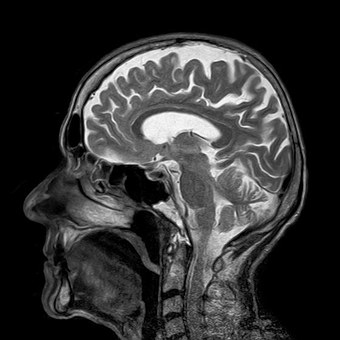

Protons at the feet are in a lower magnetic field, for example, than those at the head, and therefore they resonate at a lower frequency. The protons at the head are in a higher magnetic field, and resonate at a higher frequency. Therefore we can tell that we have water at different places in the body, and we can use this to build a picture. The tissue that has more water will appear brighter, and you start to build up an image of the water in the body. If you want to read more about the basics of MRI, take a look at the following article written in the conversation.

In the clinic, x-rays offer us the ability to image the anatomy quickly, and relatively inexpensively, but there are several reasons why an MRI may be preferred. Firstly, MRI does not use ionising radiation, like x-rays, and is often thought to be a safer imaging option. That said, the radiation dosage from a single x-ray scan is very low. X-rays give contrast in images by being reflected off bone and dense materials more than soft tissue, and hence are great for visualising bones, but it is more difficult to determine information about tissue and organs. MRI is an excellent imaging technique that allows us to build up 3D images of the body, with the ability to image deep within the patients tissue, safely and without surgery. We can see inside patients in great detail without opening them up.

An MRI scan of a body will reveal a lot of anatomical information, much more than an x-ray, because different tissues contain different amounts of water, and will appear as brighter pixels where there is more water, and darker pixels where there is less water. The contrast of the image can be made sensitive to different things though, not just the concentration of the water, by changing the lengths of time that the radio waves are collected, and other scan parameters. This can be very useful for highlighting different parts of the body.